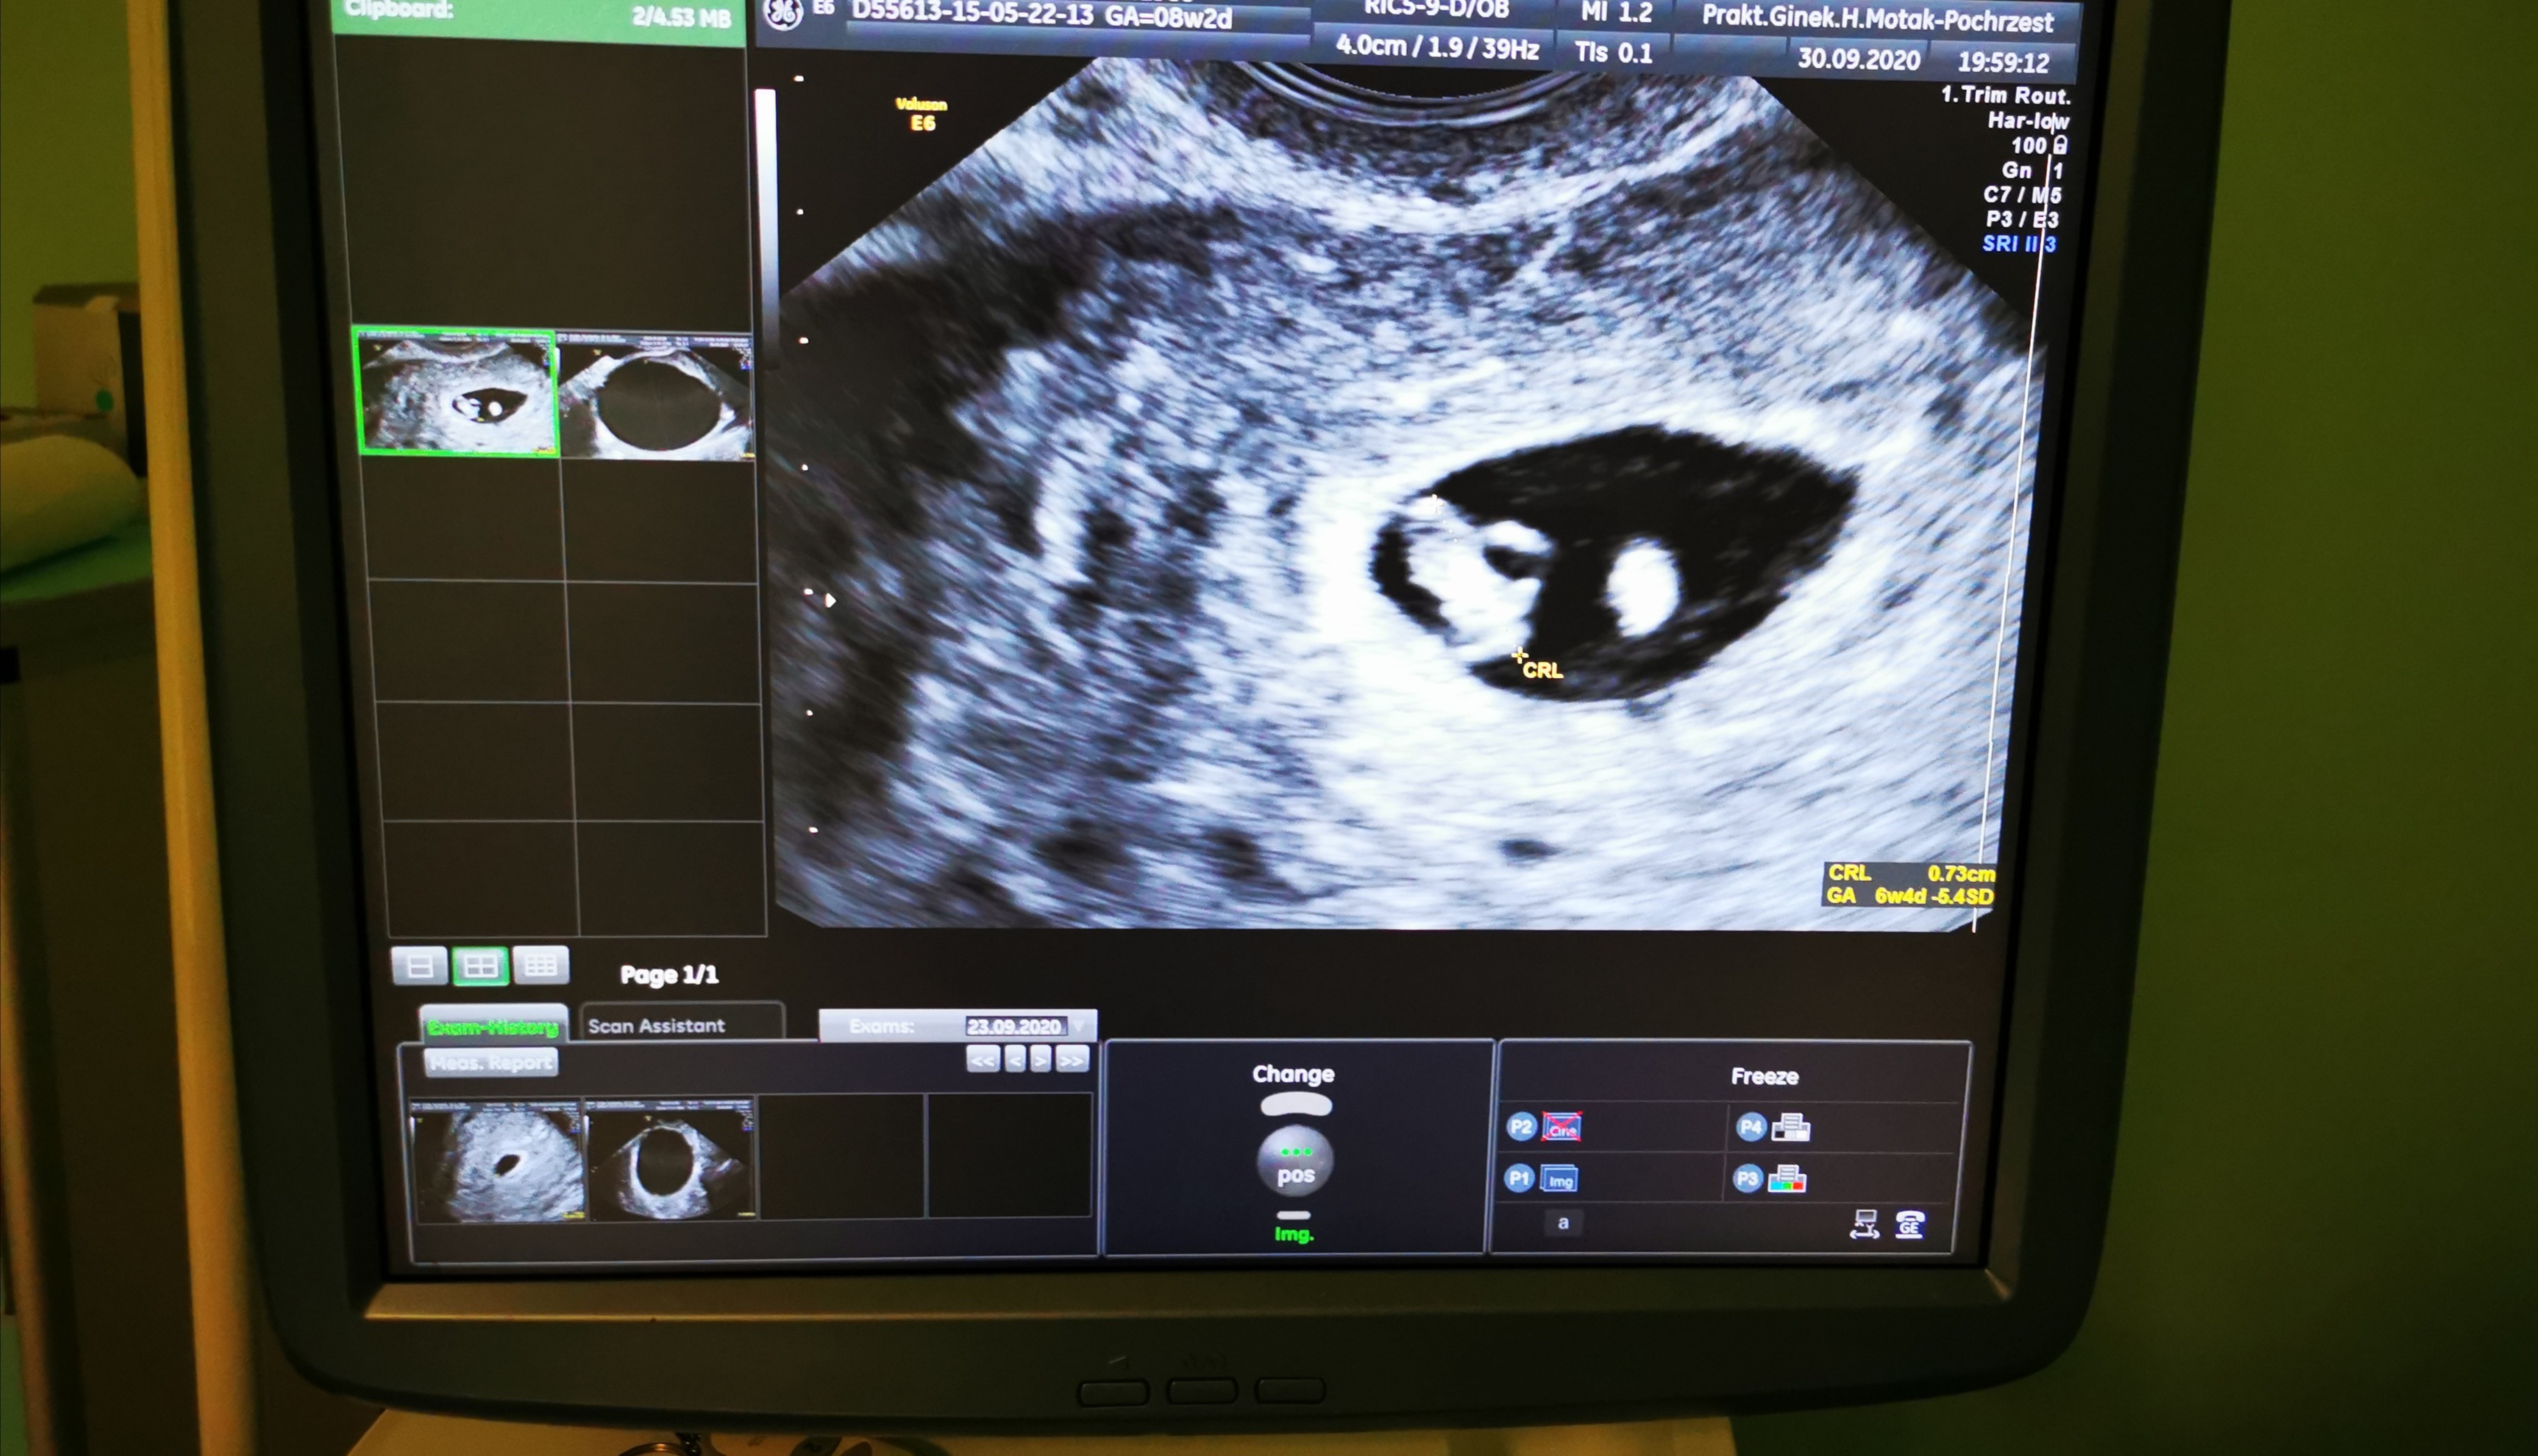

ale i pęcherzyk ciążowy 1,24cm. Według wyliczen pani gin. Od ostatniej miesiączki wychodzi 7w2d ale powiedziała że to wczesna ciąża bo w pęcherzyku nic nie ma... A boję się że on będzie pusty. Przepisała mi luteinę 50 biorę ja 2razy dziennie po 2 tabetki... Dziś robiłam badanie CA125 i od siebie betę. Obawiam się, pęcherzyk może być pusty znów. Objawów nie mam prócz tego że jestem zmęczona. Może któraś się zmagała z taką sytuacją

2 załącznik pecherzyk